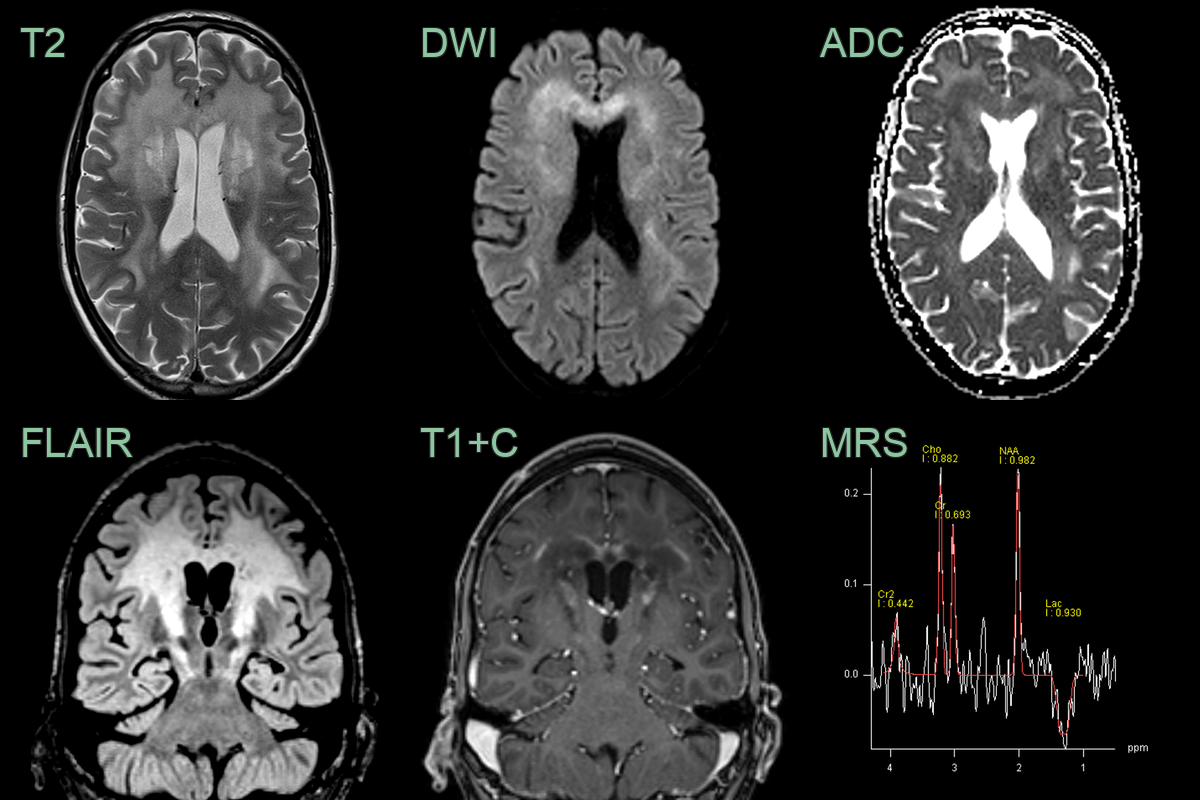

- T2/FLAIR: symmetric hyperintense signal in parieto-occipital white matter

- Splenium of corpus callosum involved early

- Corticospinal tract involvement (pyramidal tract sign)

- Auditory pathway involvement (lateral lemniscus, inferior colliculus)

- T1: hypointense in areas of demyelination

- T1+C: peripheral enhancement at advancing edge ("leading edge enhancement")

- Indicates active inflammation

- Correlates with disease progression

- DWI: restricted diffusion at actively demyelinating edge

- Facilitated diffusion in central necrotic zones

- MR Spectroscopy: elevated choline, decreased NAA, presence of lipid/lactate peaks

- A 35-year-old male presented with cognitive impairment and personality change.

- Imaging showed a diffuse anterior-predominant leukoencephalopathy with a centrifugal pattern of enhancement.

- MR spectroscopy showed a reduction in NAA and the presence of lactate.

- X-ALD was confirmed on identification of a hemizygous ABCD1 pathogenic variant on molecular genetic testing.